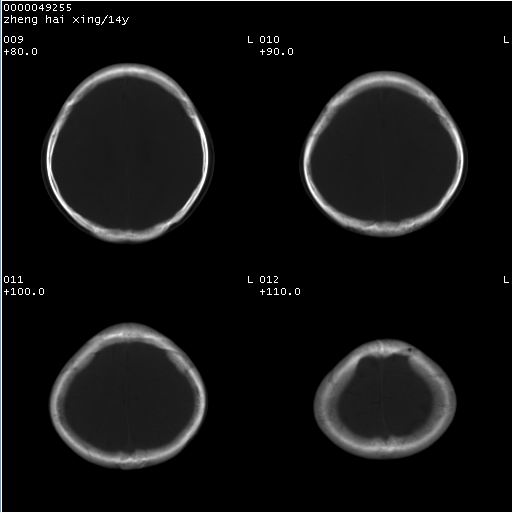

颅脑ct轴位平扫(层厚、层距均为10mm),图像如下:

双侧侧脑室之间无透明隔,双侧额角前方变扁,交角变钝。支持透明隔缺如!

透明隔缺如可为先天性缺如,亦可继发于因脑积水,脑室内压力增高,使其变薄,以至不能显示。一般无临床意义,但可并发于其他畸形或作为隔—视综合征的组成部分。